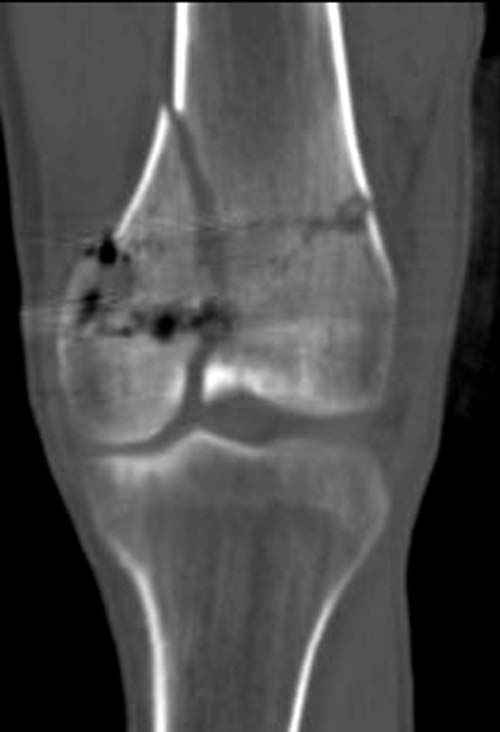

По Густило и Андерсену все high-energy переломы являются III не зависимо от степени повреждения мягких тканей. Plating такого перелома на второй день кажется немного рискованным хотя "победителей не судят". Судя по КТ, медиальный мыщелок стабильный, насколько необходимо было его фиксировать?

Идеальная репозиция?! -На снимочке A-P проeкции видна "зазубрина" по суставной поверхности, латеральный снимок - тоже не идеально.